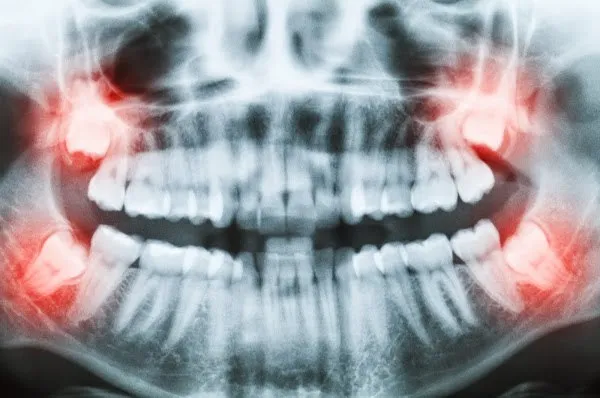

- Quando, por meio de radiografias, observamos que o mau posicionamento do siso representa risco eminente de cárie para o dente vizinho;

- Quando, por meio de radiografias, observamos que o mau posicionamento do siso representa risco eminente de reabsorção da raiz do dente vizinho;

Existem cirurgias que podem ser bem rápidas e outras que podem demorar bastante, isso varia principalmente pela posição do dente.Por isso é essencial exames complementares como a panorâmica.

Além disso, existem casos mais complicados que necessitamos realizar uma tomografia. Nesses exames vamos examinar primeiramente a posição do siso, ele pode estar na posição "normal" ou em "pé", ou seja,como todo outro dente.

Também com a tomografia podemos ver a relação das raízes com o nervo alveolar inferior.

Existem casos onde a raiz pode estar muito perto do nervo podendo causar parestesia transitória,